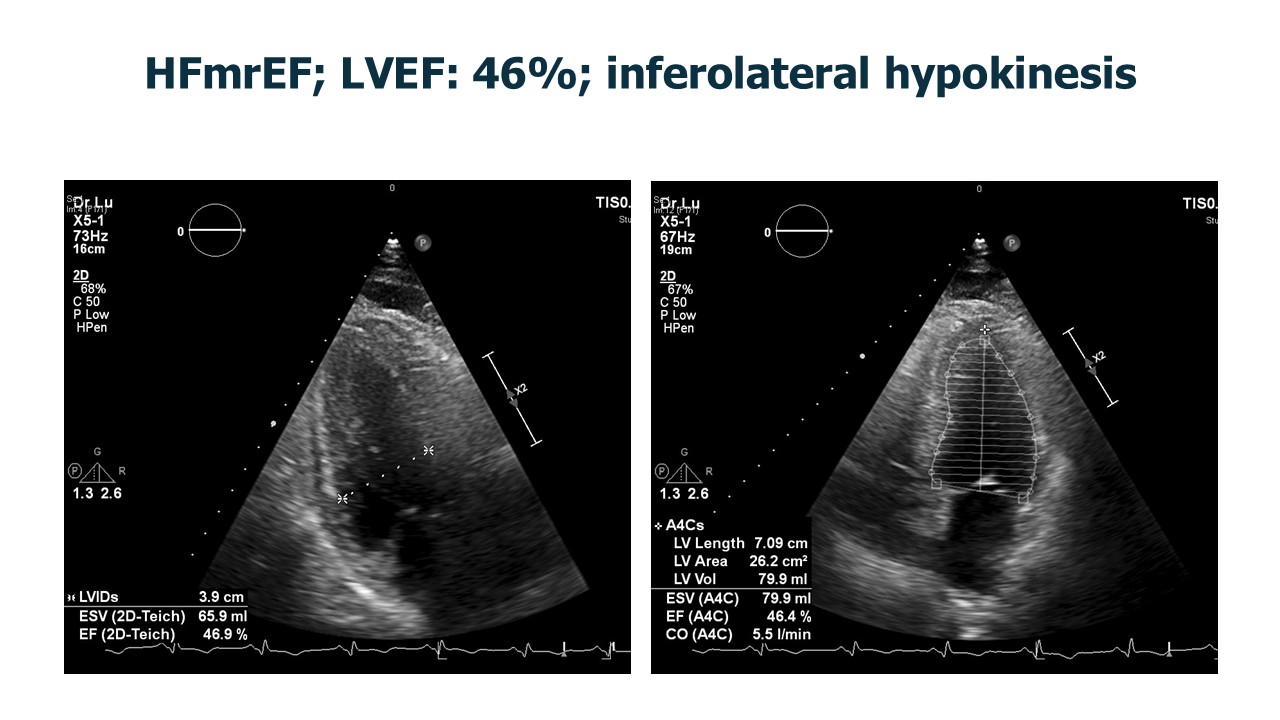

Complete blood count and renal function tests were within normal limits. Glycated hemoglobin was 5.7%. Lipid profile showed total cholesterol 157 mg/dL and low-density lipoprotein 99 mg/dL. B-type natriuretic peptide was elevated at 545 pg/mL. ECG demonstrated T-wave inversion over inferior leads, and echocardiogram revealed mildly reduced ejection fraction of 46% with inferolateral wall hypokinesis.